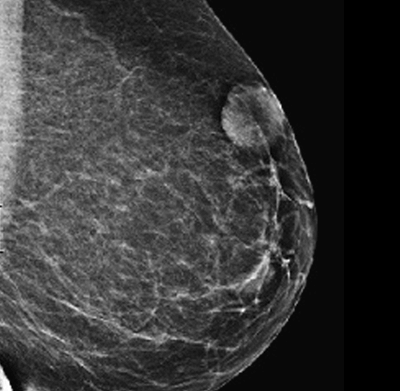

A ecografia mamária é um exame de ecografia destinado ao estudo da mama. É um óptimo exame para estudo das glândulas mamárias quer, em algumas situações, como exame diagnóstico de primeira linha, quer como complemento de outros exames, em particular da mamografia.

Durante o exame a paciente estará deitada. É-lhe colocado gel próprio para ecografia no seio e o exame é feito percorrendo os seios com a sonda ecográfica. É um exame indolor e não irradiante, que utiliza os ultra-sons e que pode trazer informações complementares de grande importância. Fornece dados quanto à textura do estroma mamário e permite caracterizar uma opacidade nodular quanto à sua natureza sólida ou quística e fornecer as suas características estruturais e dimensões. Não há, habitualmente, inconveniente em se executada em qualquer altura do ciclo menstrual, contudo ser for particularmente sensível, deverá optar por realizar o exame após o período menstrual.